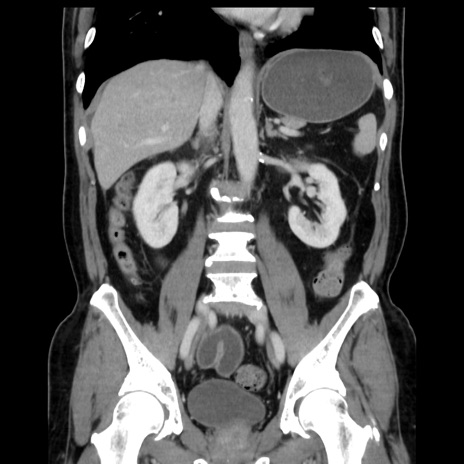

症例16(冠状断像)

【症例】 70歳代男性

【主訴】 腹痛、嘔吐

【現病歴】 約1ヶ月前より間欠的に腹痛と嘔吐あり、当院消化器内科を受診したところCTで多発する肝臓のLDAを指摘され、精査中であった。以降は消化器症状は安定していたが、2日前より嘔気と腹痛があり、同日より排便・排ガスが消失した。改善認めず、 本日、救急外来を受診した。

【既往歴】 大腸ポリープ切除後。

【身体所見】意識清明・会話良好、BT 36.3℃、BP 127/80mmHg、 P 80bpm、腹部:膨満あり、平坦・軟、上腹部正中および下腹部正中に圧痛あり、反跳痛なし、筋性防御なし。

【データ】WBC 7200、CRP 0.77

横断像